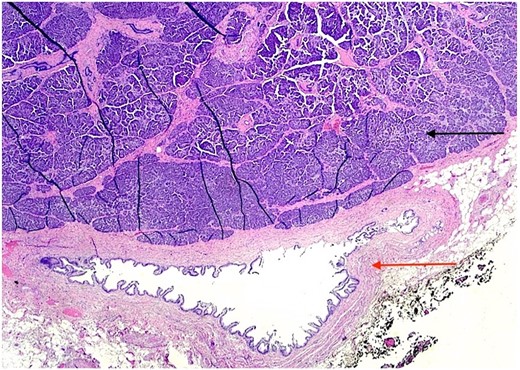

The patient underwent an elective laparoscopic cholecystectomy. During the surgery, findings were consistent with chronic cholecystitis. No abnormalities were visible upon gross inspection. Postoperatively, the patient recovered well and was discharged on the same day. The macroscopic histopathological examination revealed an intact GB with pink serosa. The mucosa was yellow-red without focal lesions. The microscopy showed chronic cholecystitis and the presence of a 1 cm focal nodule in the GB wall compatible with ectopic pancreatic parenchyma containing only acinar and ductal components (Figs 2–3). There was no evidence of dysplasia or malignant transformation in the analyzed sections. Since no malignancy was found among the EPT, there was no need for further treatment.

H & E stain 20×: Ectopic pancreatic parenchyma (black arrow), present in the gallbladder wall, composed of mucosa with underlying muscularis and adventitia (red arrow).